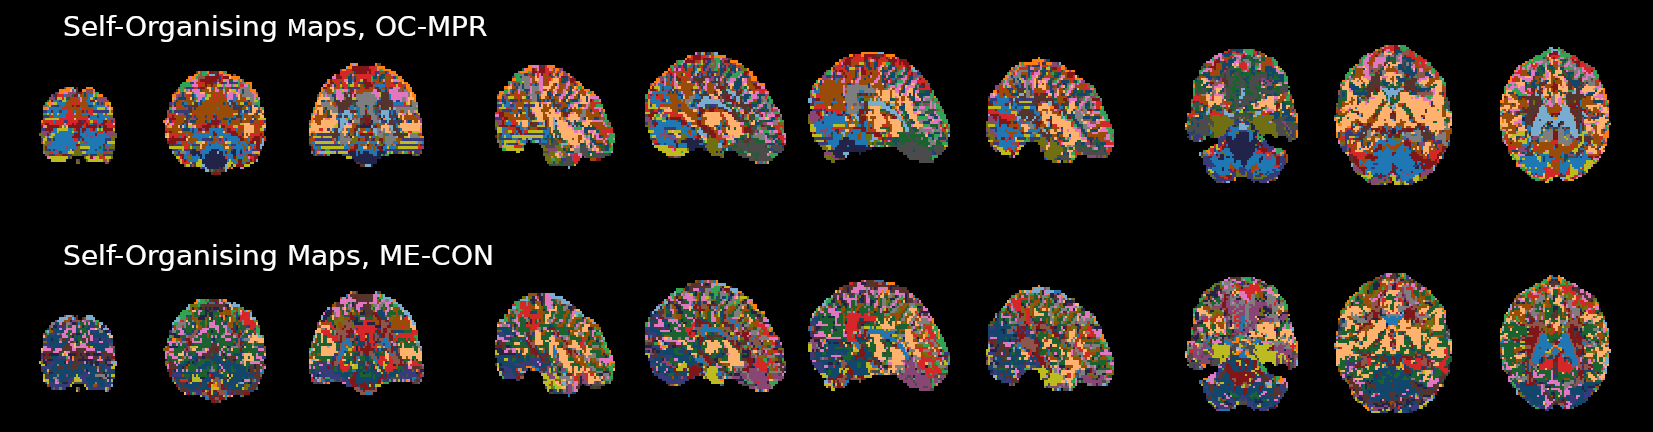

OC-MPR vs ME-CON

ME-CON should be better than OC-MPR in temporal-dependent application

Example of application: timeseries clustering (Self-Organising Maps, 20 clusters)

Submitted to ISMRM 2022

In data characterised by global responses and high motion collinearity, such as CVR, a conservative ICA-based approach best removes motion-related effects, while obtaining reliable responses, but a simple optimal combination of ME data provides similar estimations

However, further examinations are required to translate these observations to paradigms with lower collinear motion and more focal responses (e.g. functional task), or in which there is no task information available (e.g. rest)

An ICA-based conservative denoising improves BH-induced CVR mapping, but a simpler optimal combination of ME data could be already sufficient.